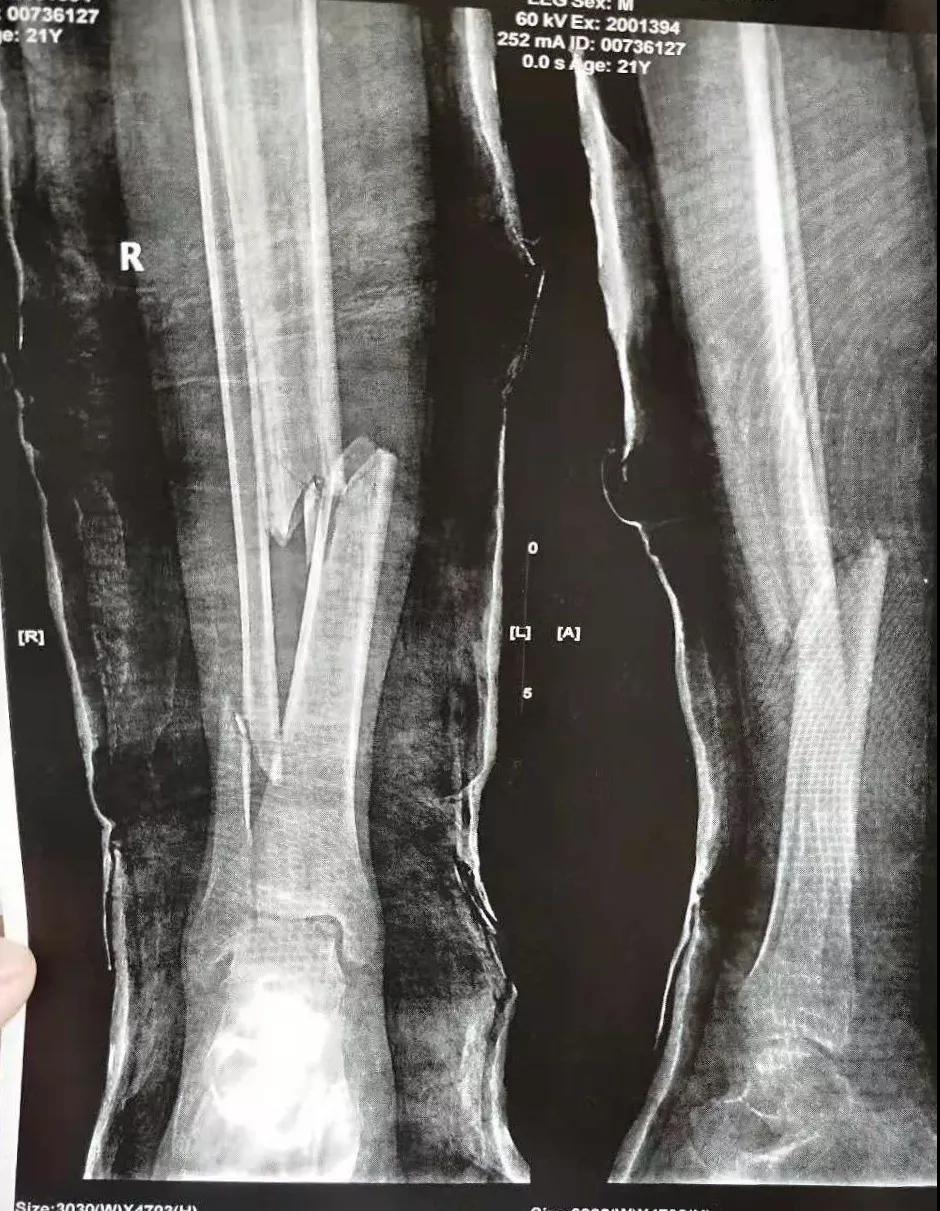

这名21岁的男性患者一个月前因车祸致伤,在当地某三甲医院确诊为右胫腓骨粉碎性骨折,骨折移位明显,建议手术治疗,因既往患严重慢性再生障碍性贫血病史16年,一般状况差,需长期输注血液制品维持三系细胞水平,麻醉及手术风险极高。虽经当地积极内科治疗,患者一般状况仍差,无法耐受手术治疗。患者及家属经多方打听,抱着最后一丝希望来到色花堂 骨二科求治。

骨二科张延平主任接诊后经仔细询问病史,详细阅读近期X线、CT等病历资料,认为患者骨折移位明显,目前骨折无任何愈合迹象,若保守治疗,骨折将无法愈合,后期不能下地活动,严重影响患者生活质量。同时患者合并慢性再障,血常规结果各项指标均极低,围术期发生麻醉意外、大出血、感染等风险极高;而色花堂 作为西安市级最大的三甲综合医院,综合实力深厚,既往相关疾病治疗经验丰富,多次通过多学科诊治为合并复杂内科疾病患者保驾护航,为患者创造手术时机,提高患者生活质量,遂将患者收住院。住院后,立即成立了由张延平主任、杨寅副主任、山卉护士长、梁晨主治医师、刘邦定主治医师、李鑫护师组成的手术治疗小组。经初步检查,患者血常规结果较当地检验结果更差,三系细胞均极低,其中血小板仅为1(正常值为100-300),血红蛋白55g/L。遂立即请血研所李罡灿主任医师会诊,给予升高白细胞、纠正贫血、升高血小板等治疗,经积极治疗患者血常规各项指标均较入院时改善。张延平主任再次组织由血研所李罡灿主任医师、麻醉科崔晓岗主任、感染科付建军主任、药剂科韩小年副主任药师等参加的术前讨论。讨论后一致认为患者目前各项指标虽然较入院时改善,但因其慢性再障病史长,骨髓造血及储备能力极差,围术期发生大出血、伤口感染甚至全身感染等风险仍极高,术中及术后需准备大量血小板防止大出血,同时需高度警惕手术切口、取骨区术后发生感染。为尽快为患者施行手术,治疗小组积极联系输血科为患者备血,并为患者制定了围术期抗感染方案;在色花堂 输血科存血量严重不足的状态时,输血科张养民主任亲自联系市中心血站为患者准备手术中及术后所需的血小板制品。手术小组为患者制定了周密的手术方案及风险预案,10月31日,在麻醉科王永宏副主任医师、手术室高洁、赵耀护师的配合下,为患者施行了右胫骨粉碎性骨折切开复位、髂骨取骨植骨内固定术,手术历时70分钟,安全返回病房。术后患者渗血多,1周内连续每日平均渗血超过100ml,并出现发烧,最高39℃,复查血常规三系细胞较术前再次明显降低。李罡灿主任医师、付建军主任、韩小年副主任药师多次来科会诊,及时调整患者的治疗方案,输血科再次为患者的救治提供了强有力的支援和保障。在山卉护士长带领的护理团队精心护理下,患者未发生压疮等卧床并发症。目前该患者术后恢复良好,已出院进行下一步康复治疗。